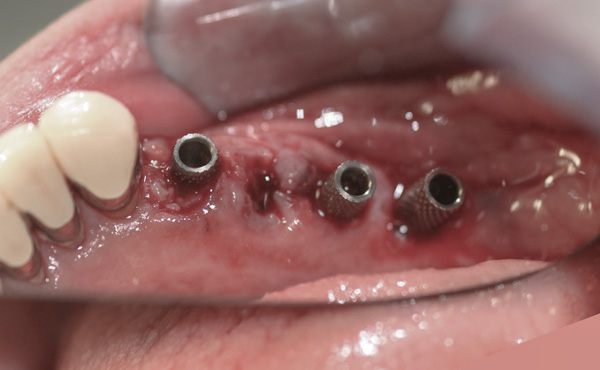

Background: In this case, the patient had a failing mandibular and maxillary dentition due to caries secondary to radiation-induced xerostomia. The patient had had a radical neck dissection to remove a squamous cell carcinoma of the throat 9 years prior to his prosthodontic consultation with the authors. The patient reported a history of radiation therapy following surgery, but did not have a shielding stent. A staged approach was used so as to avoid removable prosthetics on his severely dry soft tissues. He chose to treat his mandibular issues first. Figure 9 shows healing abutments next to the temporarily retained natural teeth, and Figure 10 shows the first-stage custom abutments inserted with relatively good gingival contour and no recession. Recession was clearly seen around all first-stage abutments following adjacent extractions and second-stage implant placement (Figure 11).

Figure 9 Healing abutments.

Figure 9

Figure 10  First-stage custom abutments.

Figure 10

Figure 11 Recession evident around first-stage abutments following adjacent extractions and second-stage implant placement.

Figure 11